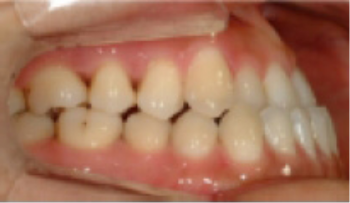

• 총생(Crowding) 치아가 삐뚤게 남.

Before

After